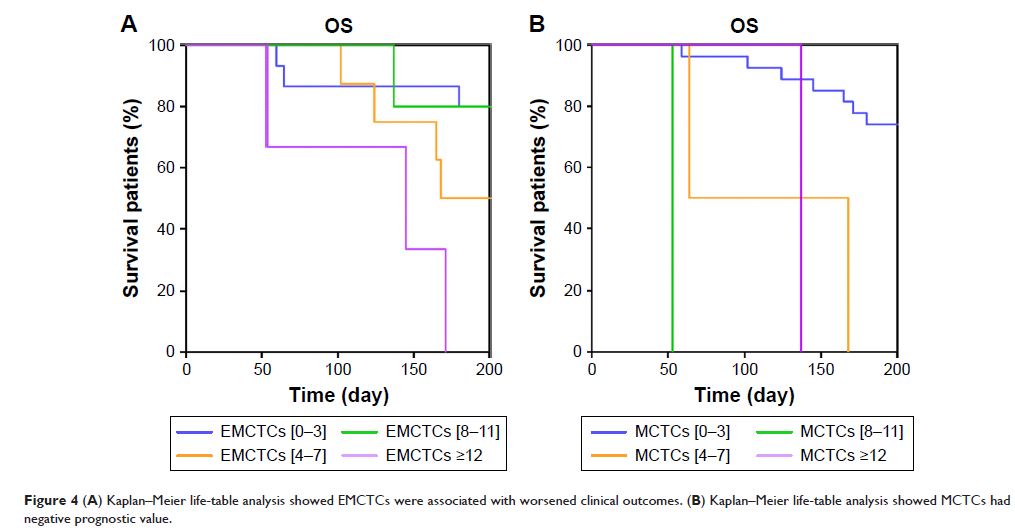

Original Research

在器官肿瘤转移、预后和 T 淋巴细胞介导的免疫应答中循环肿瘤细胞的特征

- 作者:Wen-Wen Sun, Zhi-Hong Xu, Peng Lian, Bei-Li Gao, Jia-An Hu

- 期刊:OncoTargets and Therapy